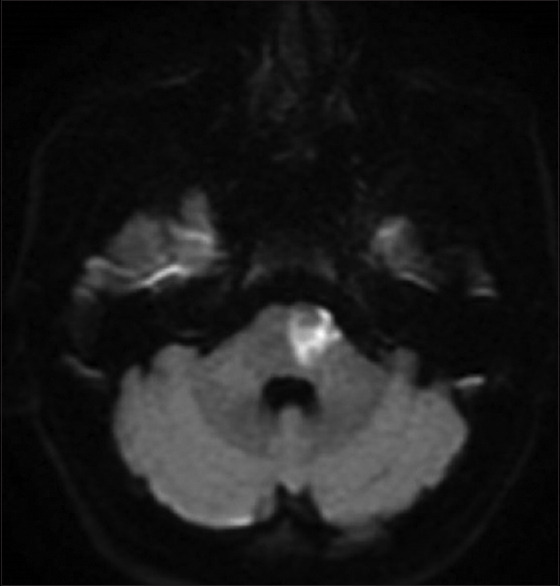

背景:对于动脉粥样硬化性或微动脉粥样硬化性急性缺血性卒中患者,替罗非班在 3 个月后实现功能独立方面优于阿司匹林。由于静脉溶栓(IVT)在治疗前脉络膜或旁侧桥脑梗死(ACI/PPI)3个月后实现功能独立方面不优于阿司匹林,我们旨在比较接受静脉溶栓加替罗非班(IVT + T)和单纯接受替罗非班治疗急性ACI/PPI的高加索患者的疗效:我们对 2020 年 12 月 1 日至 2023 年 4 月 30 日期间在我院卒中单元接受治疗的 ACI/PPI 患者(年龄≥18 岁)进行了回顾性研究,这些患者在症状出现 9 小时内或在卒中症状苏醒后接受了治疗干预。3个月时改良Rankin量表(mRS)≤1为主要终点。次要终点是第7天或出院时美国国立卫生研究院卒中量表(NIHSS)≤2和72小时内术后神经功能恶化(PPND)。无症状性颅内出血(SICH)和全身大出血(MSB)是研究的安全性指标:结果:共有24名患者加入替罗非班组,43名患者加入IVT + T组。与单用替罗非班相比,IVT + T与3个月时mRS≤1的概率更高相关(调整后的几率比[aOR],8.79;95%置信区间[CI],2.06-37.52;P = 0.003),与第7天或出院时美国国立卫生研究院卒中量表≤2相关(aOR,3.70;95% CI,1.05-12.99;P = 0.041)。两组患者在预防术后神经功能恶化方面无明显差异。IVT+T组发生了1例SICH和2例MSB,而替罗非班组没有发生SICH和MSB。IVT+T组出现一例院内死亡:我们的研究结果表明,对于急性 ACI/PPI 的高加索患者来说,IVT + T 可能是安全有效的。

Methods: A retrospective study was conducted in patients aged ≥ 18 years with ACI/PPI treated in our stroke unit between December 1, 2020, and April 30, 2023, who received therapeutic intervention within 9 hours of symptom onset or after awakening with stroke symptoms. Modified Rankin Scale (mRS) ≤ 1 at 3 months was the primary endpoint. Secondary endpoints were National Institutes of Health Stroke Scale (NIHSS) ≤ 2 at day 7 or discharge and post-procedural neurological deterioration (PPND) within 72 hours. Symptomatic intracranial hemorrhage (SICH) and major systemic bleeding (MSB) were the safety measures of the study.